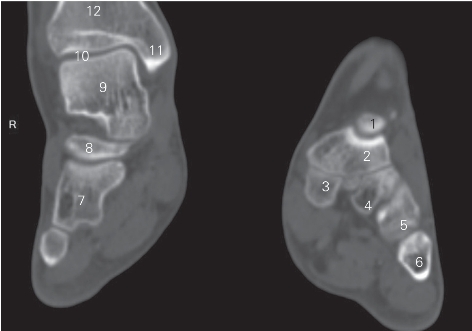

图5-40 经踝关节后份横断层CT图像(骨窗)

1 胫骨 tibia 2 踝关节 ankle joint

3 距骨头 head of talus 4 舟骨 scaproid bone

5 骰骨 cuboid bone 6 第5跖骨 5th metatarsal bone

7 跟骨 calcaneus 8 距下关节 subtalar joint

9 距骨 talus 10 腓骨 fibula

图5-41 经踝关节前份的横断层CT图像(骨窗)

1 距骨头 head of talus 2 舟骨 navicular bone

3 内侧楔骨 medial cuneiform bone

4 中间楔骨 intermediate cuneiform bone

5 外侧楔骨 lateral cuneiform bone 6 第5跖骨 5th metatarsal bone

7 骰骨 cuboid bone 8 跟骨 calcaneus

9 距骨 talus 10 踝关节 ankle joint

11 内踝 medial malleolus 12 胫骨 tibia

图5-42 经足底的冠状断层CT图像(骨窗)

1 中间楔骨 intermediate cuneiform bone 2 舟骨 navicular bone

3 跟骨 calcaneus 4 骰骨 cuboid bone

5 外侧楔骨 lateral cuneiform bone 6 内侧楔骨 medial cuneiform bone